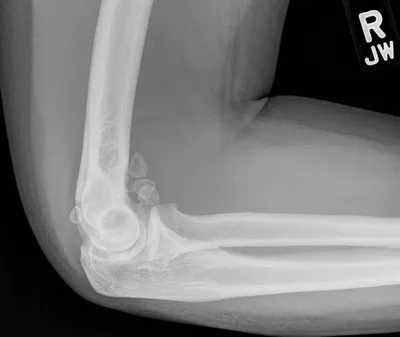

Synovial Osteochondromatosis of Elbow

Elbow

4/10/2026